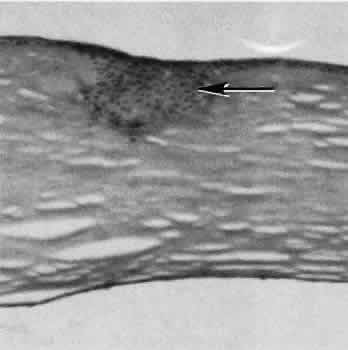

| Successful wound healing in the eye is a precise, ordered series of events